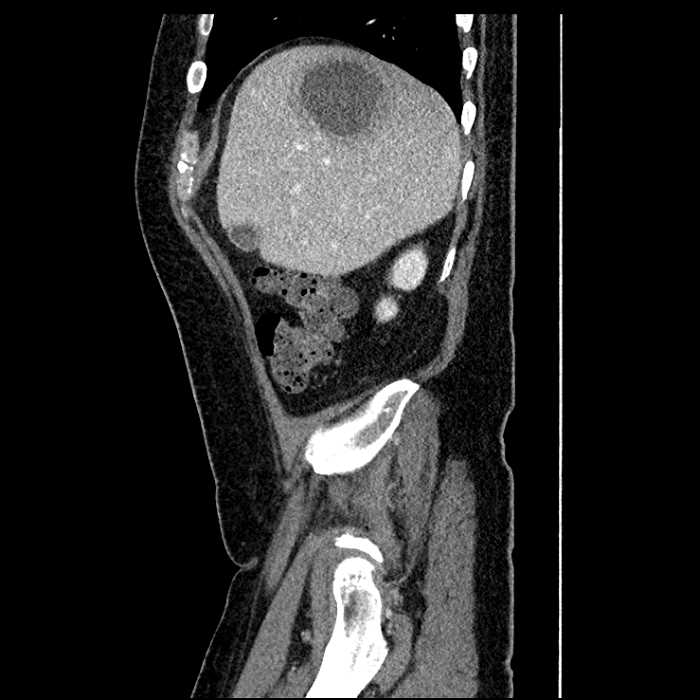

• Large fluid density structure in hepatic segments 7 and 8 measuring 10 x 7 x 7 cm with internal septation and circumferential ill-defined low density compatible with edema

• Hepatic abscess

Acute sigmoid diverticulitis complicated by a small contained perforation and a large abscess in the right hepatic lobe. Additional small subcapsular abscesses along the anterior margin of the left hepatic lobe.

• The classic CT imaging appearance is a double target sign with internal low density surrounded by an internal enhancing rim (capsule) and a low density external rim (edema)

Hepatic abscess showing the double target sign with low density internally surrounded by a thin inner enhancing rim (red arrow) and ill-defined outer low density rim (yellow arrow). Blue arrow indicates an internal septation. Red arrows: additional smaller subcapsular abscesses. Red arrow: focal contained perforation associated with diverticulitis.